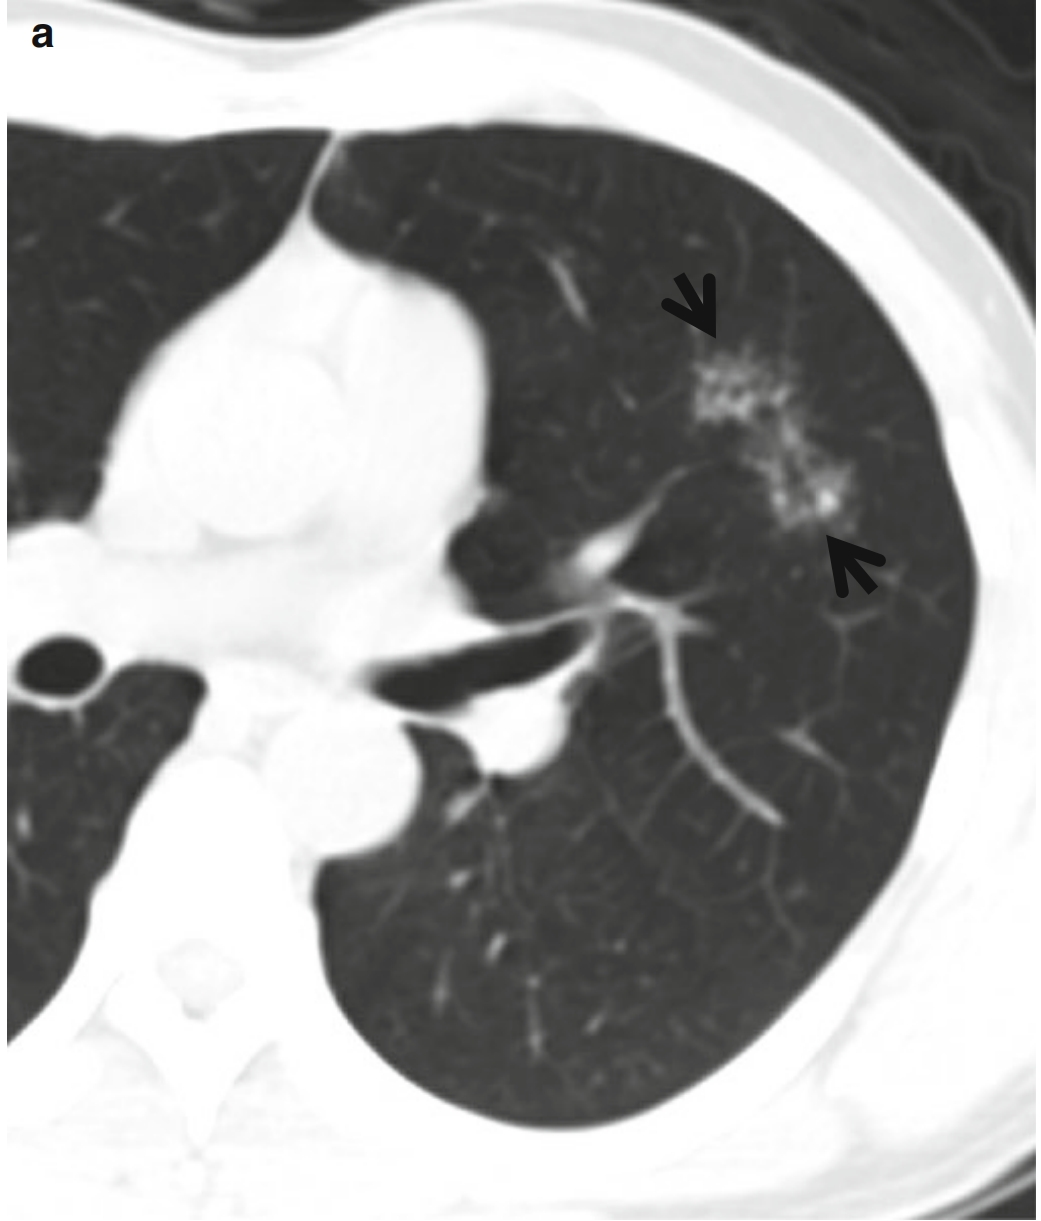

图1,CT星系征。男,23岁、肺结节病患者。连续薄层CT扫描(层厚=2.5mm)于右肺上叶支气管水平可见多发星系征(箭头所示),由多个小结节和周围多发非常小的卫星病灶组成、以右肺上叶最为明显。纵隔窗(此处未给出)可见纵隔和双侧肺门增大的淋巴结影。

图2 CT星系征。

患者男性,44 岁,活动性肺结核。

(a.b)连续CT扫描(层厚=5.0 mm,低剂量模式)于右中间段支气管水平,可见左肺上叶上舌段CT星系征(箭头所示)。在层厚相对较厚的CT图像上。需要注意的是,不能把星系征看成磨玻璃密度影而诊断为浸润性肺腺癌。